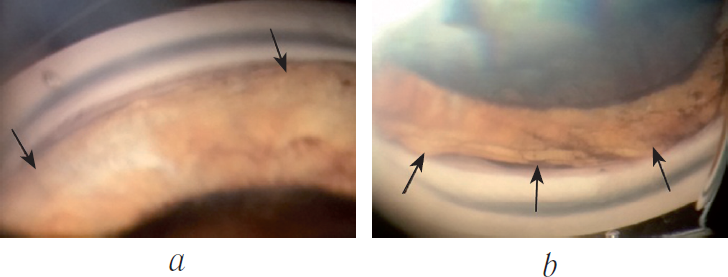

При контрольном осмотре через 2 недели после СУР отмечалась отрицательная динамика (ВГД — 10 мм рт. ст., ПЗО — 20,01 мм, по данным В-сканирования определялась плоская отслойка сосудистой оболочки от крайней периферии до экватора), по данным ОКТ: отёк макулы высотой 430 мкм; гониоскопическая картина: ЦТ отслоено от склеральной шпоры с 5.30 до 1.00 ч через 12-часовой меридиан (270°) (рис. 1, a, b). Офтальмоскопическая картина: ДЗН с нечёткими границами, отёчный, э/д достоверно не оценить; отёк сетчатки в макулярной зоне. По результатам осмотра было принято решение о выполнении дополнительной СУР в зоне циклодиализа. Вторые сутки послеоперационного периода характеризовались подъёмом ВГД до 32 мм рт. ст., которое удалось снизить до 21 мм рт. ст. путём применения вышеупомянутых гипотензивных препаратов.

Рис. 1. Пациент Ш., 35 лет. Гониоскопическая картина циклодиализа до операции, меридиан 6 (а) и 12 ч (b)

В течение 4 месяцев после СУР острота зрения с коррекцией равна 0,4; ВГД — 18 мм рт. ст. на фоне гипотензивной терапии. Офтальмоскопическая картина: ДЗН с чёткими границами, э/д 0,3; в макулярной зоне перераспределение пигмента. По данным В-сканирования сосудистая оболочка и сетчатка прилежат во всех отделах. Гониоскопически циклодиализ не определяется (рис. 2, a, b). ПЗО — 24 мм.